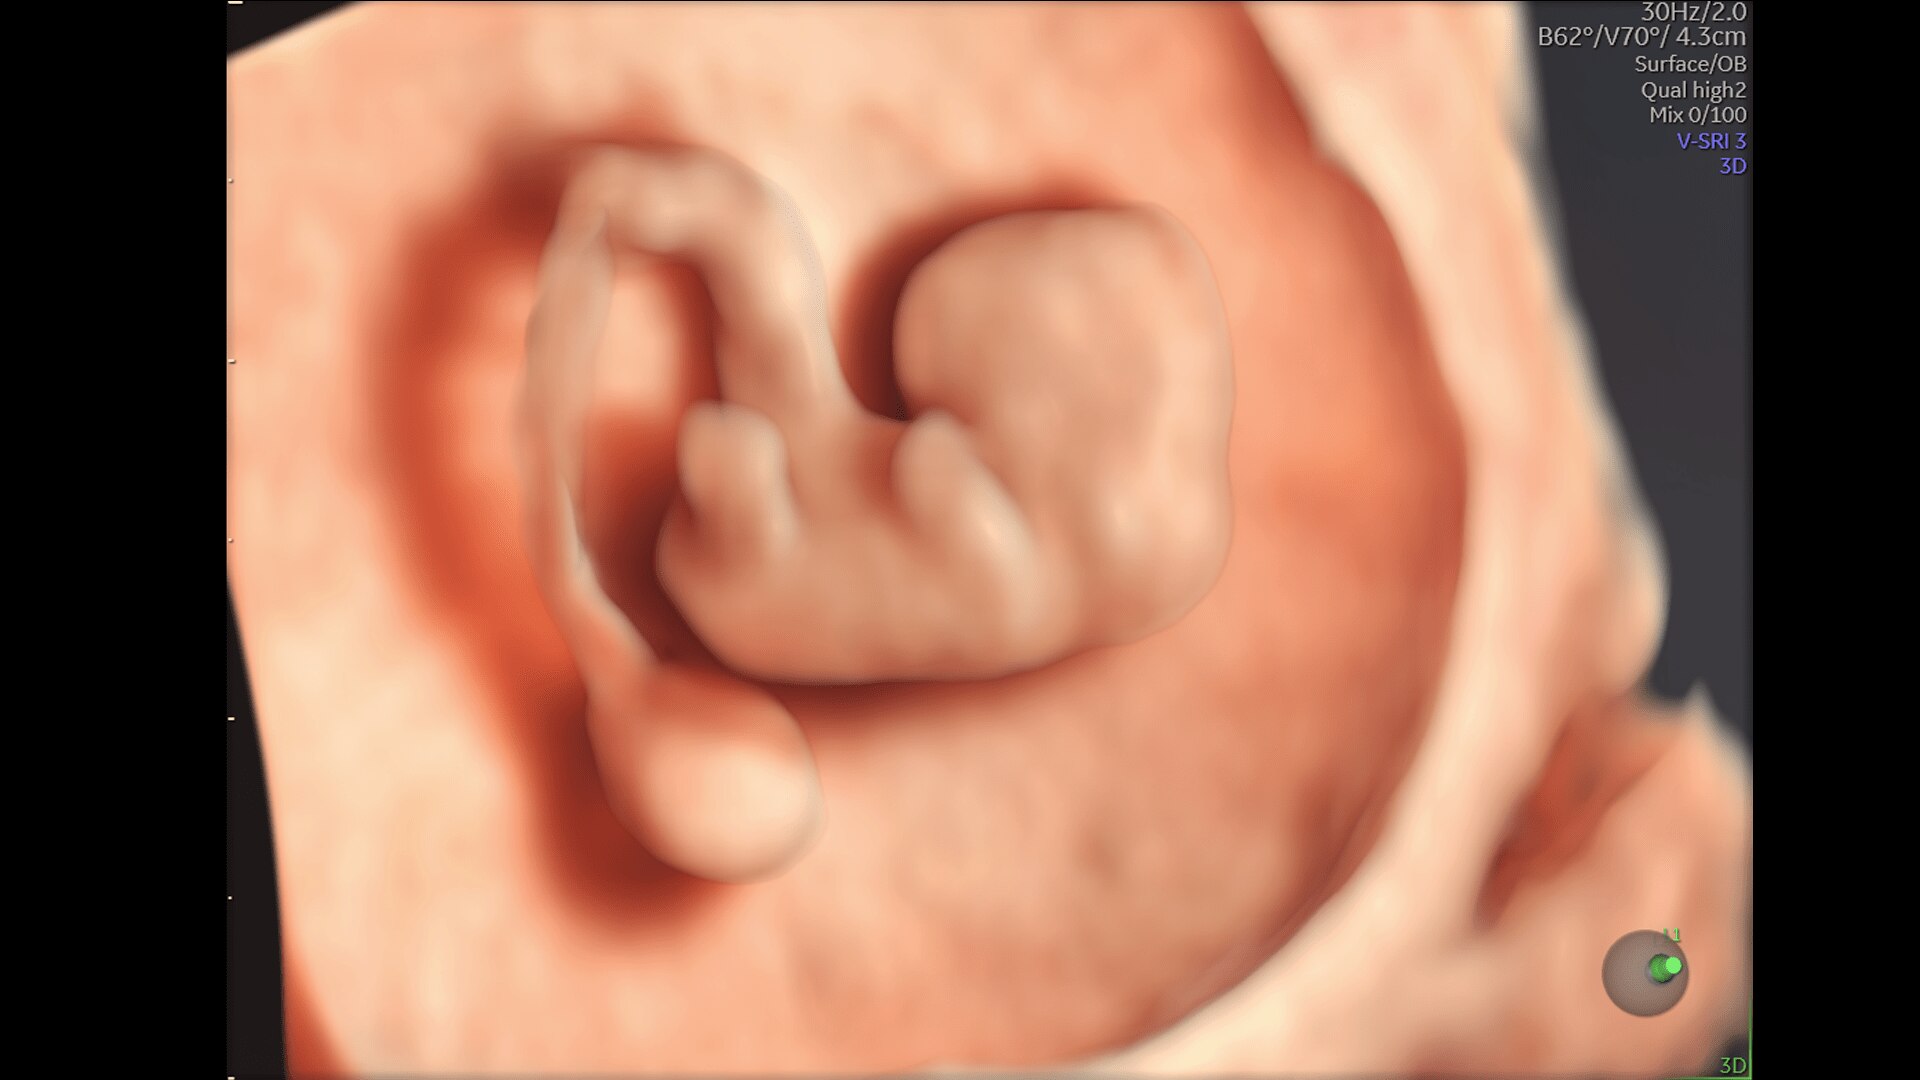

Super Fine Details

Obtain highly detailed images of the fetal brain, first trimester development, and other complex anatomy with increased axial and lateral resolution.